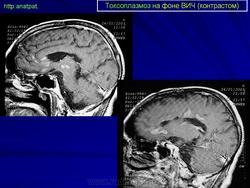

Токсоплазмоз у ВИЧ - инфицированных

Церебральный токсоплазмоз

Neurotoxoplasmosis